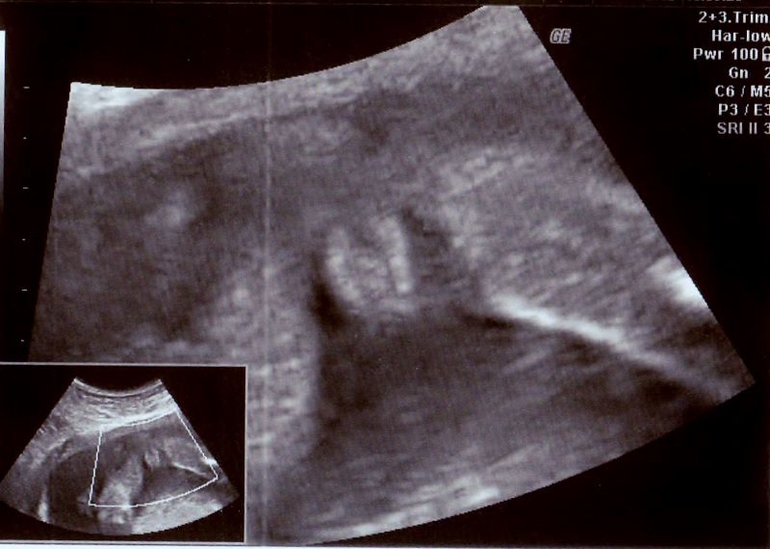

НО! Еще на очень очень маленьком сроке была у целительницы (знаю ее лет 20 и доверяю безоговорочно). Она ниточкой-иголочкой определила, что будет мальчик. Соответственно, я я уже начала покупать голубые вещички, имя выбрали. А тут, ба-бах, и спустя половину беременности врач-узист (тоже кстати доверяю безоговорочно, очень грамотная, такую еще поискать!!!) говорит: "Пол вашего малыша- ДЕВОЧКА, вот и мандариновые дольки четко видны". Без вариантов, короче.

Я в полнейшем замешательстве. Муж тоже дольки разглядел! А я не могу поверить, а самое главное, как же делать ремонт в детской. Дизайнерские обои на заказ идут в среднем 2-2,5 мес., а делать ремонт, когда дома уже появится лялька я не хочу...будут всякие грязные строители ходить и вообще строительный мусор....Но апогоеем могут стать розовые обои и внезапно родившийся.... мальчик! Как поступить? Или ткните меня носом в эти мандариновые дольки....